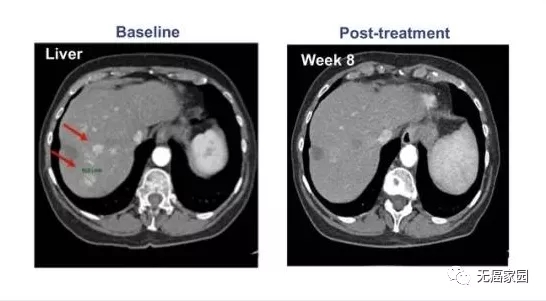

国际知名杂志《Journal of Hematology & Oncology》刊登了我国医学研究者们的一项成功改造CAR-T技术的临床研究,研究中提及的CAR-T产品选择的靶点是glypican-3(GPC3,主要是肝癌)。

其中1例晚期肝癌患者接受了瘤内注射CAR-T治疗,治疗后肝脏病灶代谢基本消失。

CAR-T细胞注射60天后,虽然2个肺部结节的尺寸没有显著的改变,但在第10天时肝脏肿瘤病变(1.2×1.3cm)显著收缩,注射GPC3-7×19 CAR-T细胞第32天后则完全消失。

患者没有任何毒性作用,并且根据 CT 上的标准实体瘤反应评估标准 (RECIST) 1.1 版进行了分期评估,显示部分缓解 (PR)。